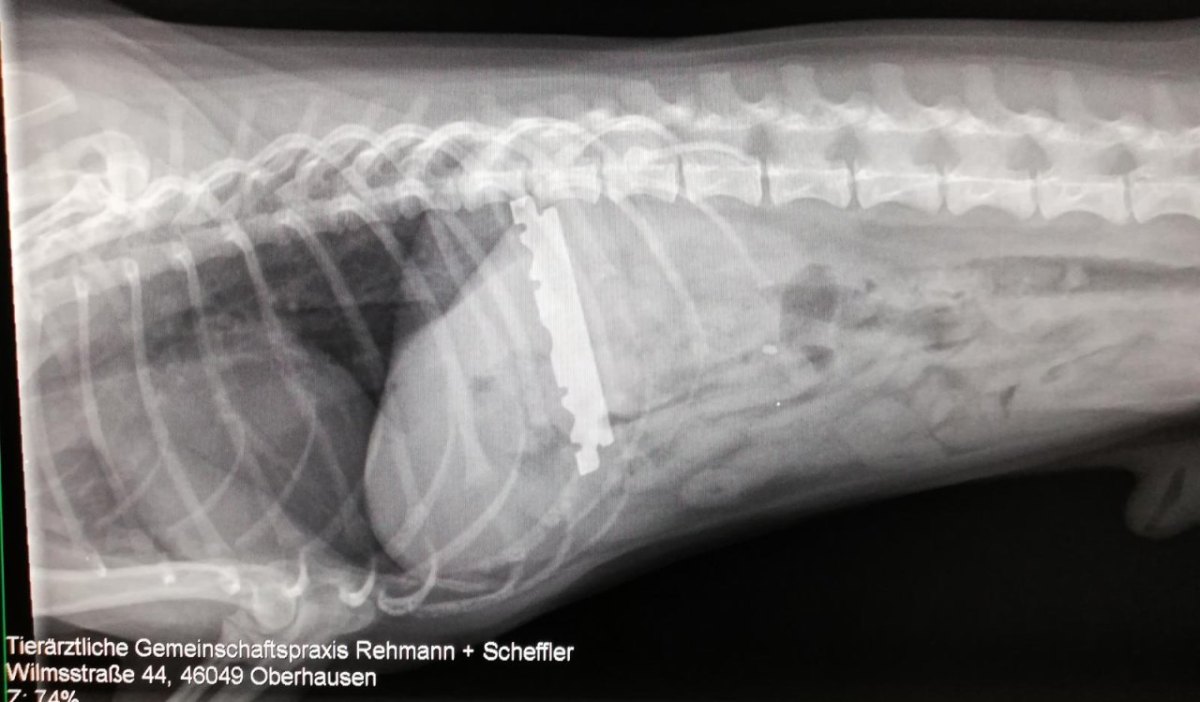

Das Röntgenbild zeigte dann die unglaubliche Ursache für die Beschwerden: Das Tier hatte eine zentimeterlange Rasierklinge im Magen.

„Hunde kommen häufig mit Magen-Darm Beschweren in unsere Praxis, nur selten verbergen sich hinter den Beschwerden solche extremen Gründe, wie eine Rasierklinge im Magen des Tieres“, so die Tierarztpraxis gegenüber DER WESTEN.

Nach einem solchen Röntgenbild müsse man jedoch eine Warnung aussprechen.